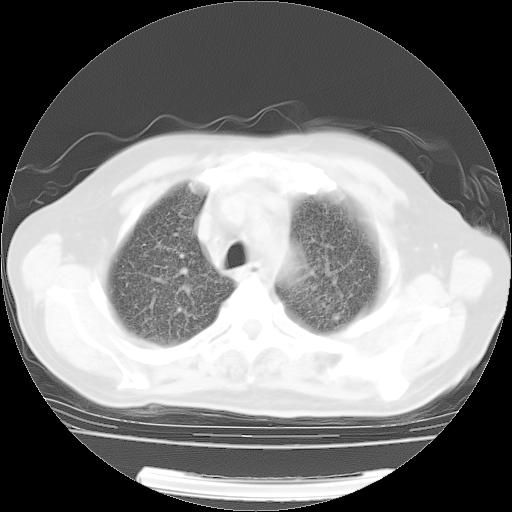

4月14日肺部CT

23.JPG

24.JPG

25.JPG

26.JPG